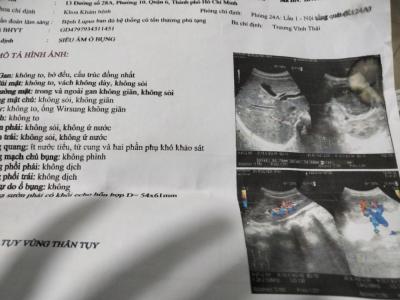

Hôm nay Mai Trâm Có liên lạc hỏi thăm tình hình sức khỏe của Cháu Trúc.thì được biết bệnh tình cháu Trúc tiến triển rất tốt. Và hiện tại phác đồ điều trị bệnh của cháu trúc 2 tuần đến khám một lần và lấy thuốc là 2 tuần mỗi lần đi như thế tầm khoảng 1 triệu tiền khám và thuốc uống.

Một số thông tin về bệnh tình của cháu Trúc và hình ảnh giấy tờ cháu Trúc đi khám bệnh gần đây nhất.

Mai Trâm xin gửi đến cả nhà cùng nắm được.